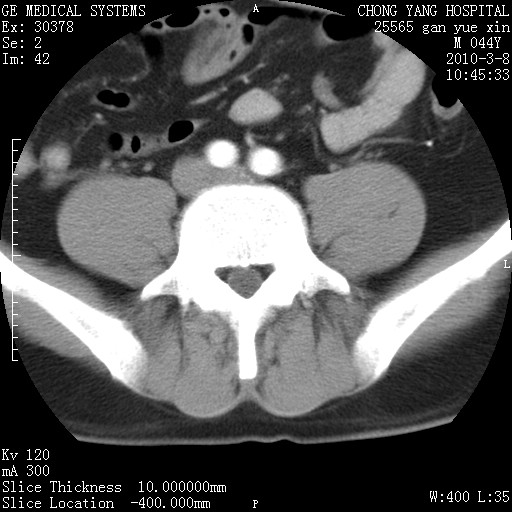

标题: CT24940:主动脉增强,典型病例。 [打印本页]

标题: CT24940:主动脉增强,典型病例。

夹层动脉瘤。

动脉夹层

夹层动脉瘤,典型

主动脉夹层。

动脉夹层的分型:

⒈debakey分型:根据主动脉夹层累及部位,分为三型:ⅰ型:原发破口位于升主动脉或主动脉弓部,夹层累及升主动脉、主动脉弓部、胸主动脉、腹主动脉大部或全部,少数可累及髂动脉。ⅱ型:原发破口位于升主动脉,夹层累及升主动脉,少数可累及部分主动脉弓。ⅲ型:原发破口位于左锁骨下动脉开口远端,根据夹层累及范围又分为ⅲa,ⅲb。ⅲa型:夹层累及胸主动脉。ⅲb型:夹层累及升主动脉、腹主动脉大部或全部。少数可累及髂动脉。

⒉stanford分型:a型:夹层累及升主动脉,无论远端范围如何。b型:夹层累及左锁骨下动脉开口以远的降主动脉。

夹层动脉瘤,少量胸水

夹层动脉瘤;左侧少量胸腔积液。

典型主动脉夹层。